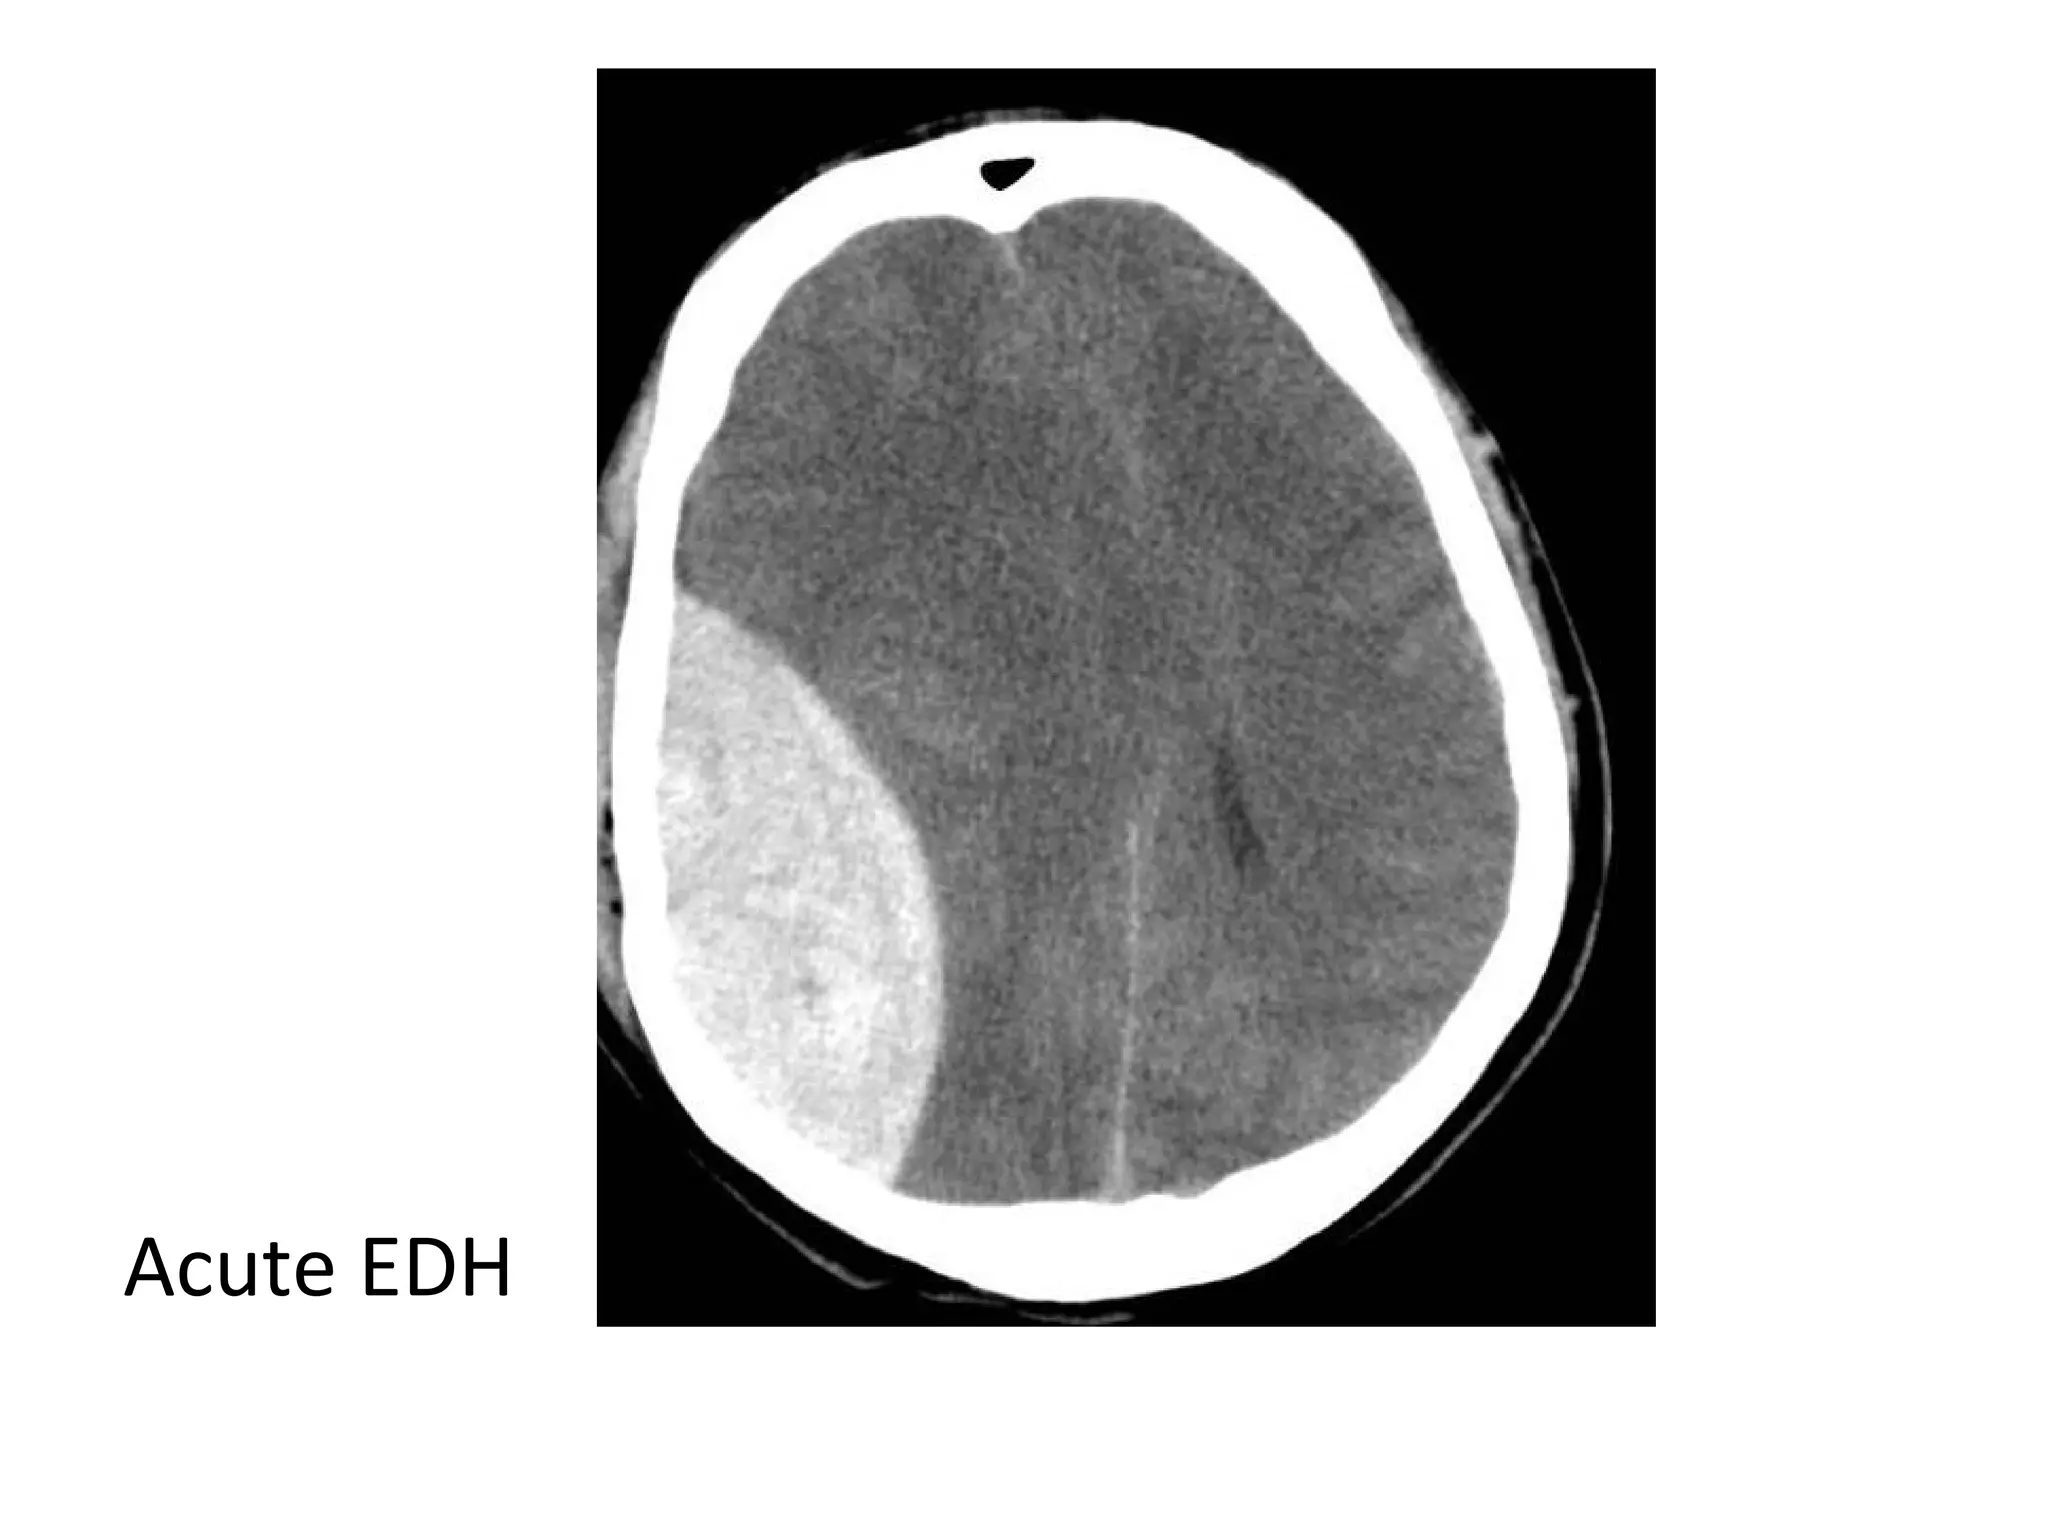

-Acute thrombus is hyperdense on precontrast CT

and expands the occluded sinus / vein (Dense

clot sign)

- Cord sign : is defined as a homogeneous ,

hyperattenuated appearance of thrombosed

venous sinuses , the hyperattenuated

appearance of the affected veins often being

Direct visualization of a clot in the cerebral veins on a non enhanced

CT scan is known as the dense clot sign

Dense clot sign in a thrombosed cortical vein